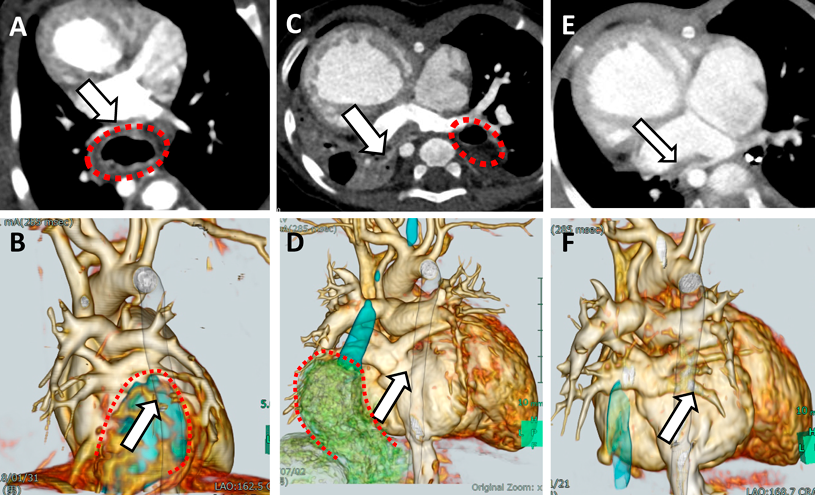

滑脱した胃と肺静脈との位置関係(Figs. 4, 5)

胸部CT画像における滑脱した胃と肺静脈との位置関係の相違を,肺静脈圧排例と非圧排例で観察し比較した.13例全例において肺静脈は共通肺静脈腔を形成し心房に接続していた.肺静脈圧排群(症例2, 3, 4, 5)では,①滑脱した胃の先進部が共通肺静脈腔と同じ高さに達している,②滑脱した胃は必ず心房椎体間に位置し,肺静脈を後方から圧排している,といった特徴を有していた.なお,下行大動脈は肺静脈圧排に関与していなかった.一方で肺静脈非圧排群では,①滑脱した胃の先進部が共通肺静脈腔の高さに達していない例(症例6, 8, 9, 12)と,②滑脱した胃の先進部が共通肺静脈腔の高さに達していても,共通肺静脈腔よりも末梢に位置している例(症例1, 7, 11)があった.肺静脈圧排群と非圧排群の特徴は,椎体の両縁から左右の肺静脈開口部へそれぞれ線を引き,その線の間に滑脱した胃が含まれるかどうかでより明確に判断できた(Fig. 4A).肺静脈圧排群では滑脱した胃は同線の間に位置した(Fig. 4A).一方で非圧排群では,滑脱した胃は同線外側に位置するか,肺静脈心房開口部とは同じCT断面で観察されず肺静脈開口部よりも腹側に位置していた(Fig. 4B).

Fig. 4 Chest CT images of all cases

If the pulmonary vein and hiatal hernia (HH) are in the same cross-section, the round shows HH (Case 1–5, 7, 11). A: In case 2–5, the pulmonary vein compression is observed. B: In case 1, 6–9, 11–12, the pulmonary vein compression is not observed.

Fig. 5 The round shows hiatal hernia (HH) and the arrow shows pulmonary vein compression by HH

Case 3: With the progression of funnel chest, the pulmonary vein continues to be compressed. Case 9: Despite progression of funnel chest, there is no compression of the pulmonary veins.

また,肺静脈圧排群のうち症例3, 4, 非圧排群のうち症例8, 9, 12では経時的な漏斗胸の増悪を認めた.肺静脈圧迫群である症例3, 4は漏斗胸の進行に伴い肺静脈圧排が持続していたが,非圧排群である症例8, 9, 12は漏斗胸の増悪にもかかわらず肺静脈圧排の出現はなかった.Fig. 5に肺静脈圧排群である症例3,非圧排群である症例9の経時的変化を示す.漏斗胸は滑脱した胃による肺静脈圧排の増幅要因として影響していた.